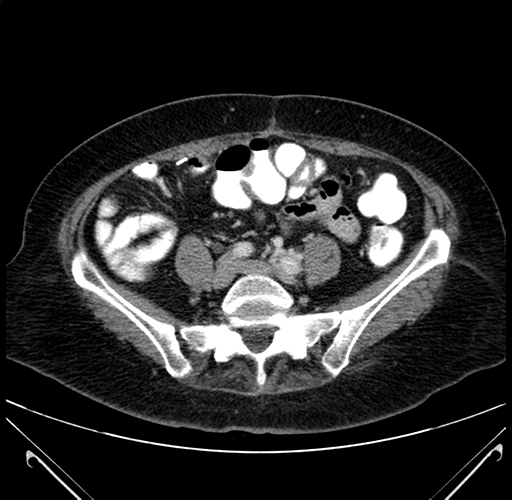

Pre-Chemo: Axial Venous

Axial Venous